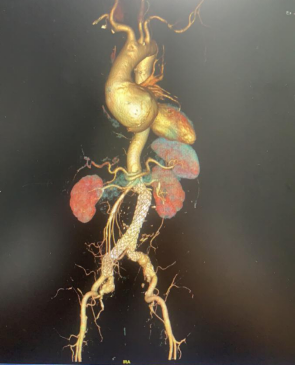

腹主动脉瘤腔内隔绝术后

术后复查的CTA:瘤消失了